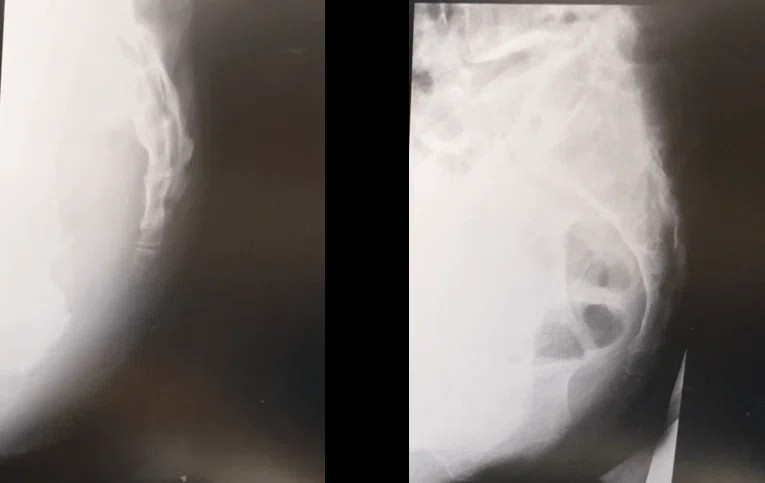

尾てい骨の痛みがある場合、整形外科などで**レントゲン検査(X線検査)**が行われることがあります。レントゲンでは主に、骨折・ひび(不全骨折)・明らかな脱臼や変形といった「骨そのものの異常」が確認対象になります。

特に、転倒して尻もちをついた直後や、強い外力が加わったあとでは、尾てい骨に骨折が起きていないかを確認する目的で撮影されるケースが多いとされています。撮影は正面像や側面像で行われ、尾骨の角度や連なり方を評価します。